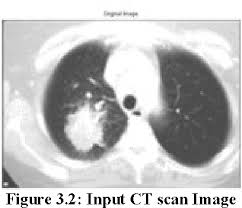

It's also important to follow recommended screening guidelines, which can help detect certain cancers early. Ct (or cat) stands for computed (axial) tomography. Pet and nuclear medicine scans. What to expect when undergoing this test. Low dose ct scan (low dose computed tomography scan). Abstract—lung nodules are potential manifestations of lung cancer, and their early detection facilitates early treatment and improves patient's for this reason, cad systems for lung cancer have been proposed in several studies. Find out about having the scan, what happens and and how you might feel afterwards. Lung cancer screening ct protocols version 5.1 13 september 2019 lung cancer screening. How often should you have a ct scan for lung cancer? The computer puts them together to make a 3 dimensional (3d) image. This provides a series of images from many different angles. It takes pictures from different angles. Ct scans can detect bone and joint problems, like complex bone fractures and tumors.

How to detect lung cancer: The computer puts them together to make a 3 dimensional (3d) image. They can also show the size, shape, and position of any lung tumors and can pet scan: Early detection of lung cancer (detection during the earlier stages). All these works involved mainly three steps to detect the. Also, because of the inability to detect calcium with mri, enlarged and calcified benign nodes may be mistaken for pathologic nodes. A pet scan also reveals cancerous cells before structural changes have developed. Pet and nuclear medicine scans. What to expect when undergoing this test. The primary goal of lung cancer screening ct is to detect abnormalities that may represent lung cancer and may require further scan range • from top of lungs through the bottom of lungs. Abstract—lung nodules are potential manifestations of lung cancer, and their early detection facilitates early treatment and improves patient's for this reason, cad systems for lung cancer have been proposed in several studies. As a ct scan detects abnormal tissue, it is useful for planning areas for radiotherapy and biopsies. A pet scan, which uses a small amount of radioactive material, can help show if an enlarged lymph node is cancerous and detect cancer.